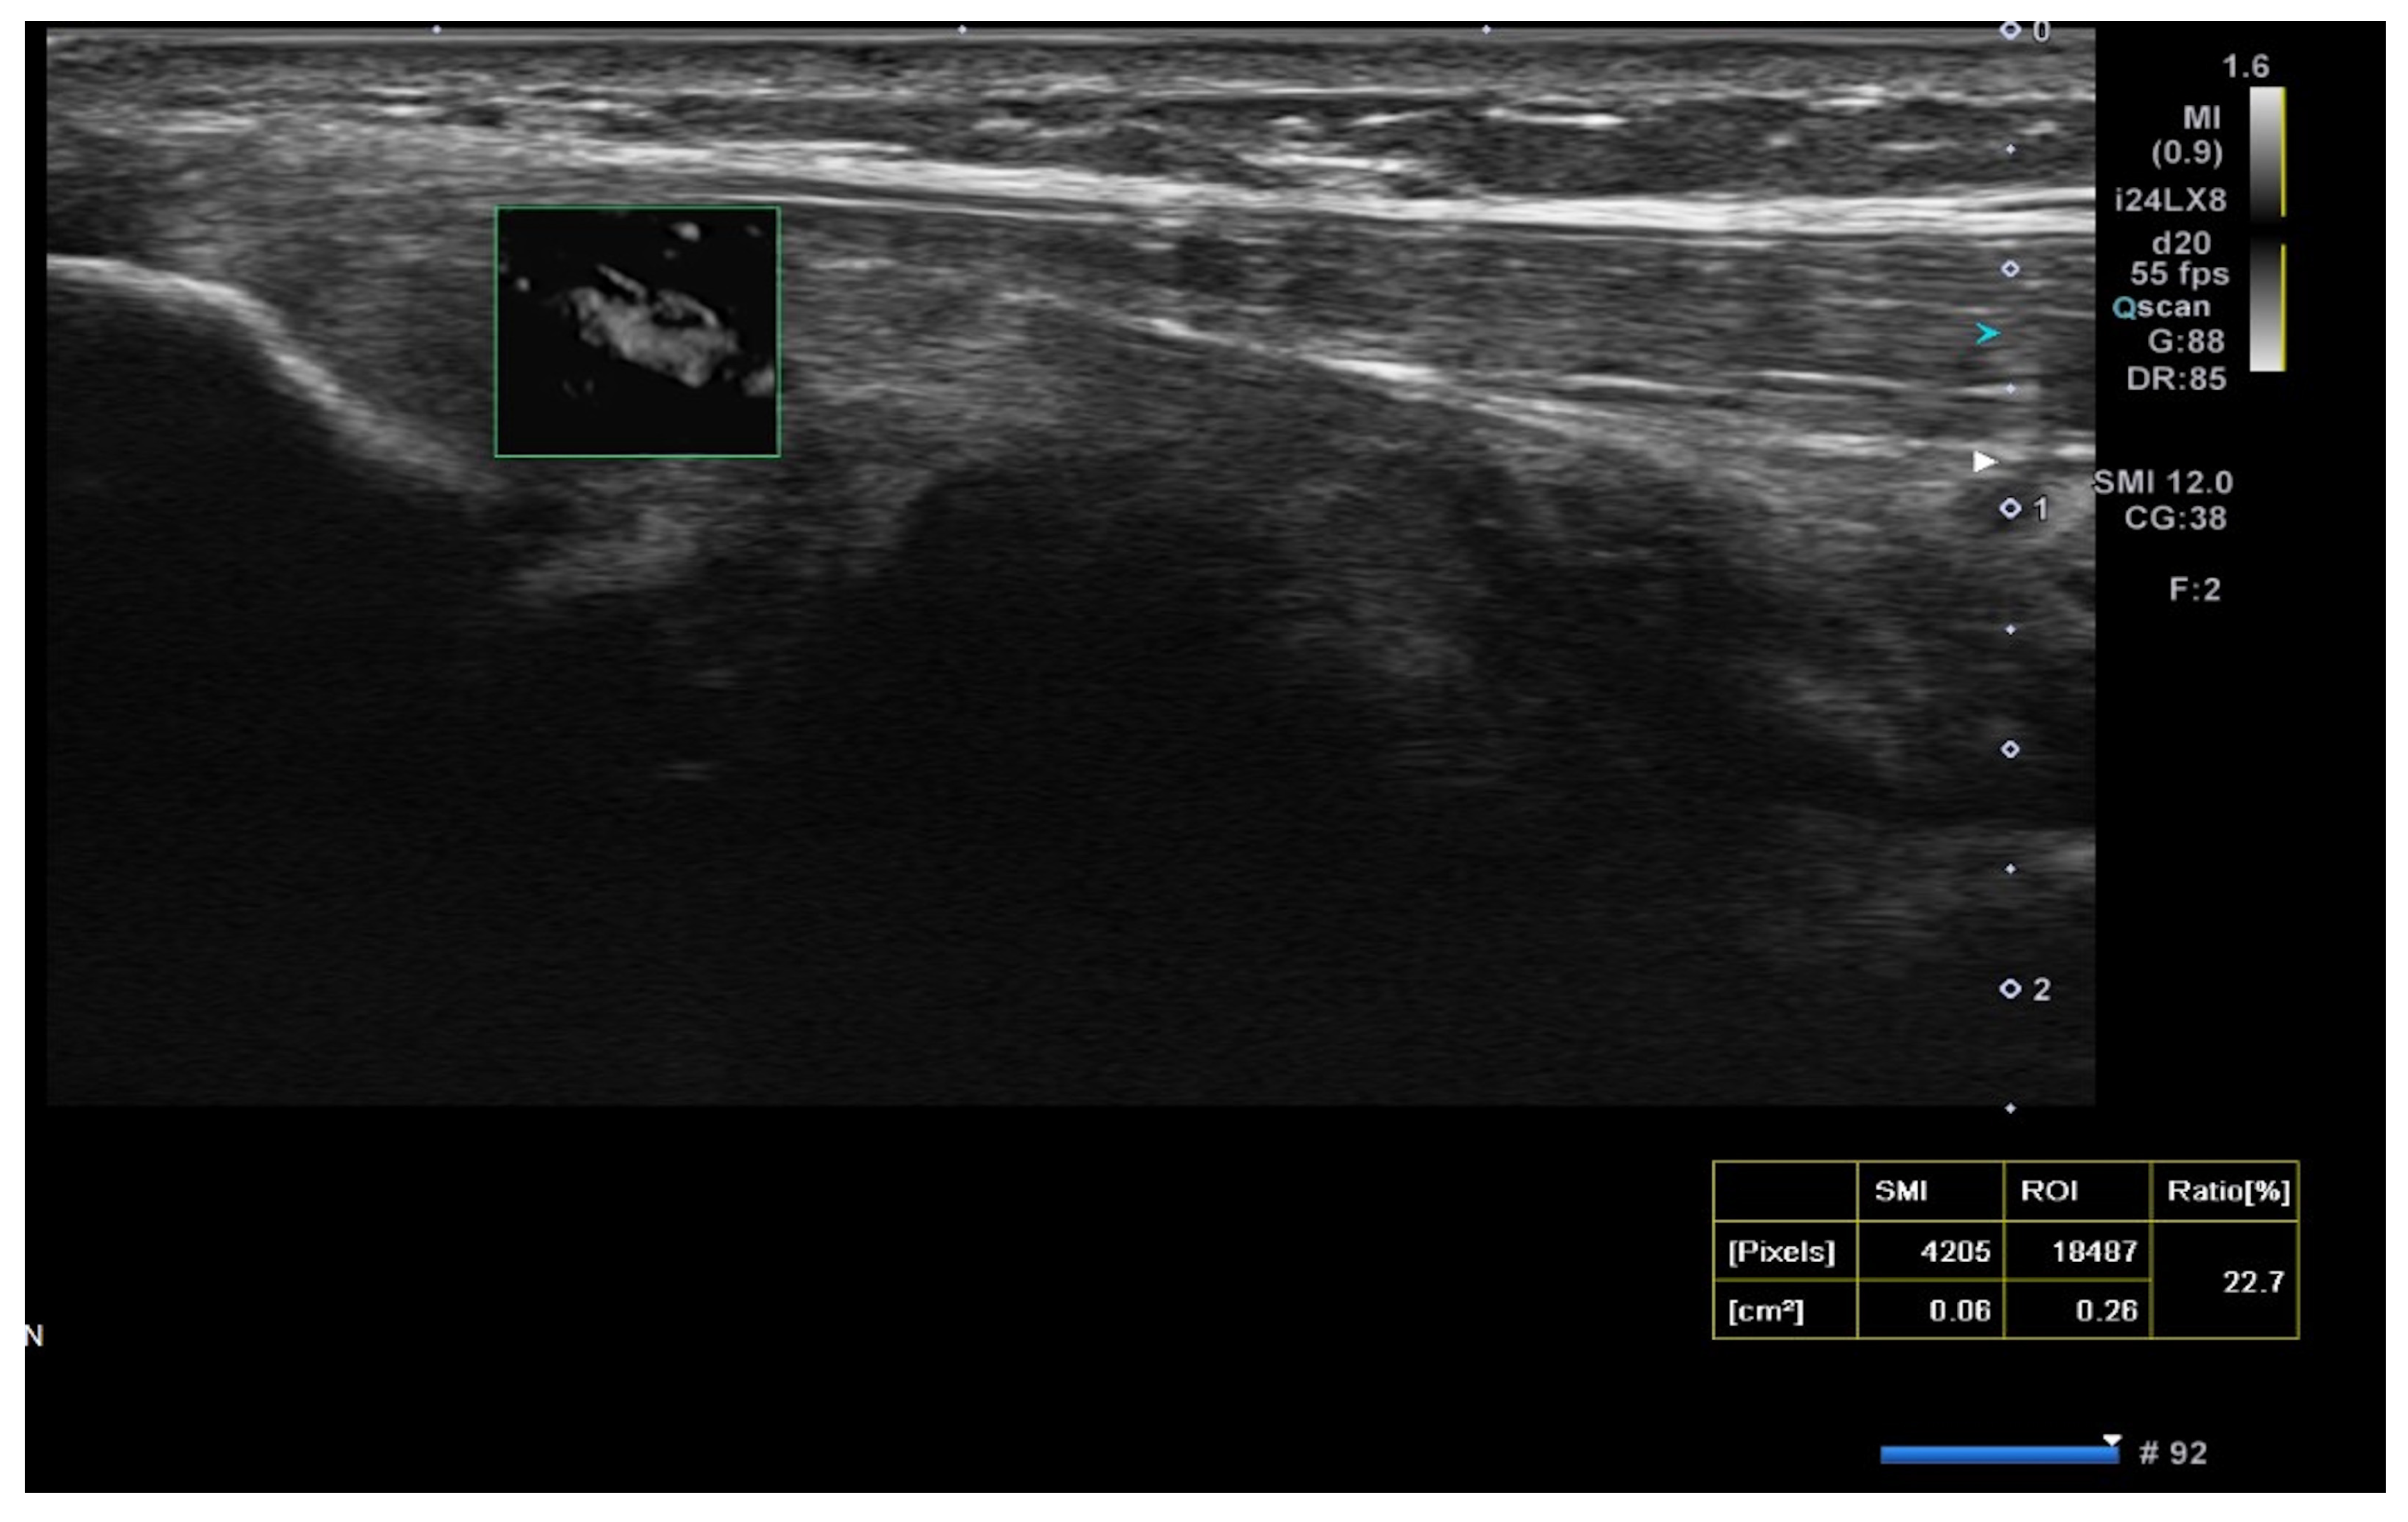

Superb microvascular imaging (SMI) was assessed alongside Doppler ultrasonography (USG) as described in the literature, allowing for a more quantitative evaluation of vascularity [21] (Figure 3).

Figure 3.

Superb microvascular imaging (SMI) in USG for lateral epicondylitis. The SMI technique enhances visualization of microvascular structures with high sensitivity, distinguishing low-velocity blood flow that may be associated with tendon inflammation and neovascularization.

The mean Doppler USG grades at baseline were 2.9 ± 1.1 in the PRP group, 1.9 ± 1.5 in the saline group, and 2.2 ± 1.4 in the glucocorticoid group, which decreased to 2.1 ± 1.4, 1.7 ± 1.4, and 1.4 ± 1, respectively, after treatment. These changes showed no correlation with clinical score improvements. Consequently, we utilized the SMI method, which is more sensitive and specific than Doppler USG grading for lateral epicondylitis, providing a more accurate demonstration of vascularity at the myotendinous junction [21].

In our study, the SMI technique was utilized for the first time in the follow-up after injection, differing from previous literature. The percentage change in SMI measurements was not significant among the glucocorticoid (9.8 ± 7.8 from 9.8 ± 9.3), saline (10.24 ± 8.4 from 9.3 ± 7.5), and PRP (7.06 ± 6.6 from 12.4 ± 6.9) groups.